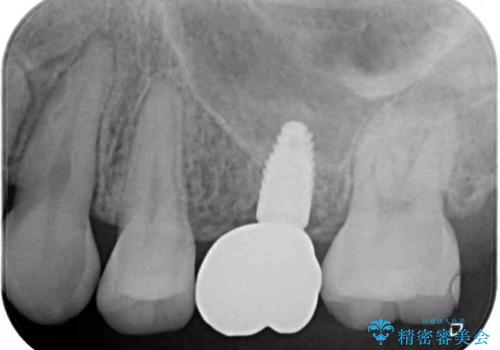

また、上顎臼歯は虫歯により抜歯されてから放置されている状態でした。

舌のトレーニングをしっかりと行っていただきながらワイヤー装置により矯正治療を行い、途中でインプラントを埋入し、矯正治療後に補綴治療を行うこととしました。